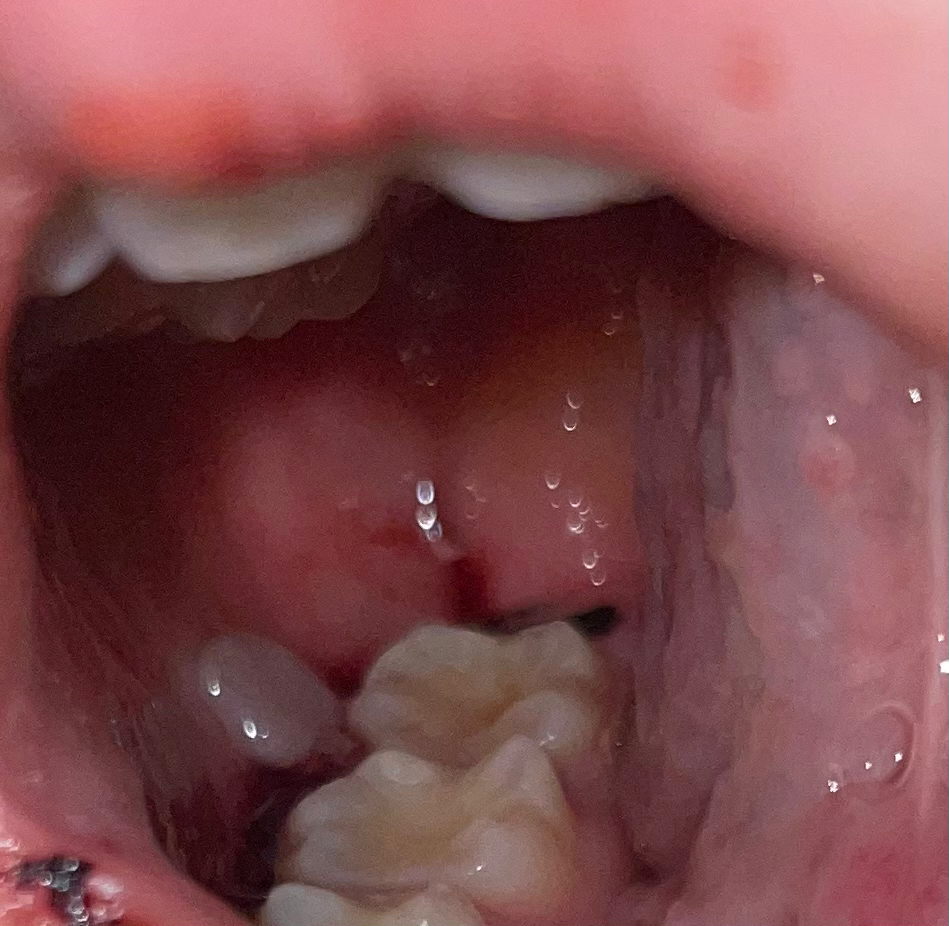

지혈이 잘 된건가요 혈병은 언제쯤 생기나요?

치아 바깥쪽으로 있는 피는 굳은피로 흐르지 않습니다..

사랑니 발치부위에서만 피가 조금씩 나오는 상태입니다(14시간동안 지혈했어요...지혈이 잘 안되는 몸)

• 1번 째 사진

발치 후 하루가 지나더라도 지금처럼 출혈이 조금씩 나타날 수 있습니다. 완전히 지혈이 된다는 것은 구강 내에서는 흔하지 않으며 타액 및 다른 음식물에 의해 조금씩 자극 될 수 있기 때문입니다. 서서히 혈병이 생기고 출혈이 조금씩 줄어들 것으로 보입니다. 물을 마셔도 되지만 계속해서 불편감이 있다면 치과 방문을 권해드립니다.

피가 흐르지 않고 피딱지가되는게 혈병입니다. 지금상태에서 지혈이 되셧다면 크게 문제는 없습니다. 압박지혈이 좋기 때문에 거즈를 꽉깨물고 있으신게 지혈에 좋습니다. 그래도 지혈이 되지 않는다면 치과에 가셔서 소독이라도 받으세요.

혈병은 지혈이 된 후 이틀차부터 생기며 현재는 괜찮은 치유상태로 보입니다 걱정하지마시고 치과에서 체크받으시면 되겠습니다

혈병은 사랑니 발치후 1~2일 안에 형성 됩니다.